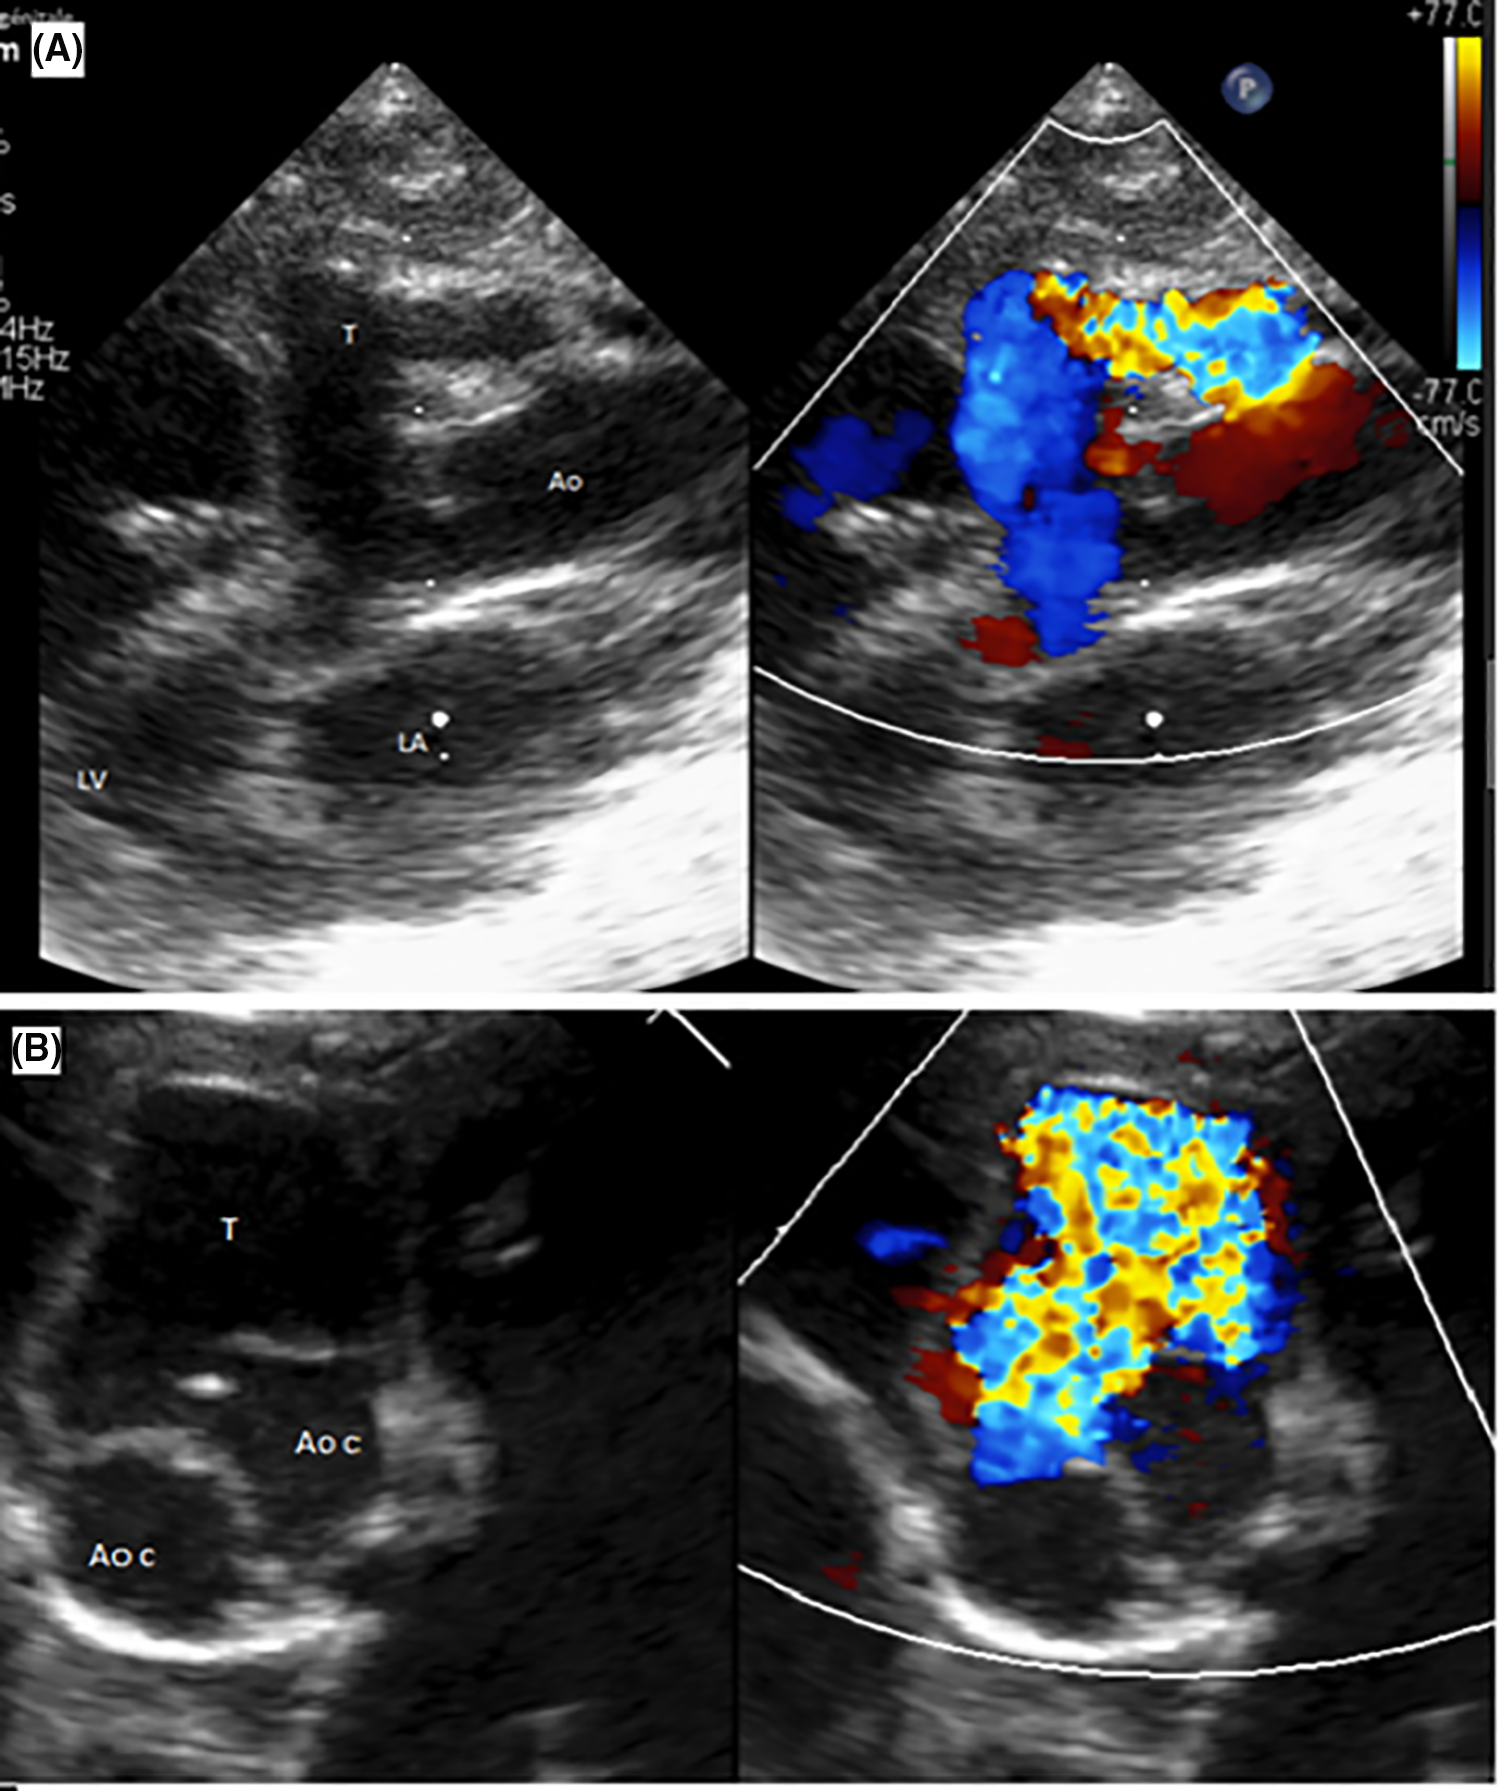

Transthoracic echocardiography (TTE) revealed several findings: a patent ductus arteriosus (PDA); an aorto-ventricular tunnel (AVT) located at the right coronary sinus, with an aortic end diameter measuring 7.4 mm and left ventricle (LV) end diameter measuring 4.7 mm (in and out); a bicuspid aortic valve without aortic valve regurgitation; a dilated left coronary ostium, with the diameter of the left main coronary artery (LCA) measuring 3.53 mm (Fig. 1); the right coronary artery (RCA) was not visualized; normal mitral valve morphology and annular diameter; a dilated LV, with a left ventricular end-diastolic diameter (LVEDd) measuring 26.8 mm (Z score 4.09), and an interventricular septum thickness of 4.65 mm (Z score 2.77). Additionally, there was left ventricular dysfunction with a left ventricular ejection fraction (LVEF) of 31%. Notably, there was flow reversal in the abdominal aorta pulsed wave Doppler, indicating diastolic runoff at 0.2 m/s.

Figure 1: Transthoracic echocardiography: Aortic regurgitation through the tunnel. (A). Parasternal long-axis view showing the tunnel with its aortic and left ventricular orifices (T: tunnel; Ao: Aorta; LV: left ventricle; LA: left atrium). (B). Parasternal short axis view showing the relationship of the tunnel with the aortic valve (T: tunnel; Ao c: Aortic cusp)